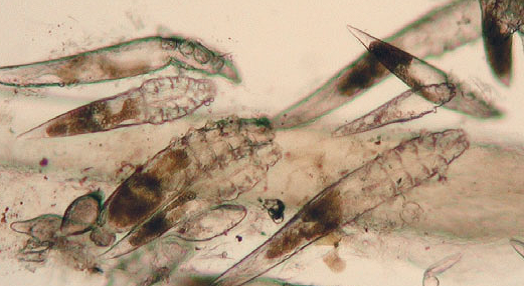

Возбудителем демодекоза является

Возбудителем демодекоза является 116 фотографий